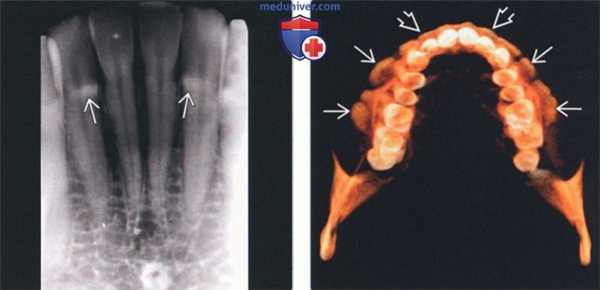

(Слева) На периапикальной рентгенограмме области средней трети корней премоляров слева определяется четко отграниченный рентгеноконтрастный участок. Такая локализация типична для нижнечелюстных валиков, хотя валики большого размера могут распространяться кзади к молярам и кпереди к резцам. Обратите внимание на отсутствие просветления на периферии. Четкие и ровные края помогают отличить валик от идиопатического остеосклероза.

(Справа) На периапикальной рентгенограмме центральных резцов нижней челюсти определяются типично выглядящие двухсторонние нижнечелюстные валики.

3. Рентгенография при нижнечелюстном валике:

• Интраоральные рентгенограммы:

о Двухсторонние хорошо отграниченные рентгеноконтрастные участки в области средней трети корней премоляров нижней челюсти

4. КТ при нижнечелюстном валике:

• КЛКТ:

о Двухсторонние экзофитные участки высокой плотности с язычной стороны в области премоляров нижней челюсти

(Слева) На аксиальной КЛКТ визуализируются большие фестончатые рентгеноконтрастные разрастания, представляющие собой нижнечелюстные валики.

(Справа) На корональной КЛКТ определяется сдавление языка огромными нижнечелюстными валиками. Валики покрыты тонкой слизистой оболочкой, которая может травмироваться. При хроническом воспалении или нарушении функции валики удаляются. Обратите внимание на верхне и нижнечелюстные щечные экзостозы, которые часто сочетаются с нижнечелюстными валиками.